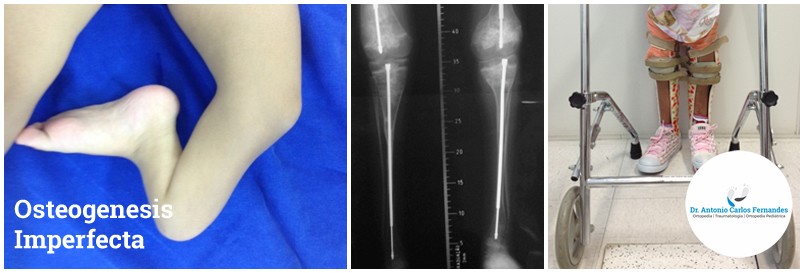

Além das fraturas frequentes observamos ossos arqueados, fraqueza muscular, atraso no desenvolvimento motor. Outras características são a baixa estatura, face de aspecto triangular, escleras (globo ocular) azuladas, dentes quebradiços, perda auditiva, escoliose, dores ósseas, etc.

O tratamento das fraturas é individualizado e na maioria das vezes não cirúrgico, através de imobilizações com gessos ou órteses. As cirurgias ortopédicas podem estar indicadas para a correção de deformidades e arqueamentos ósseos, permitindo melhor posicionamento e maior segurança para o treino de marcha. Neste caso podem ser utilizadas hastes telescopadas, que acompanham o crescimento dos ossos longos e diminuem a possibilidade novos procedimentos.